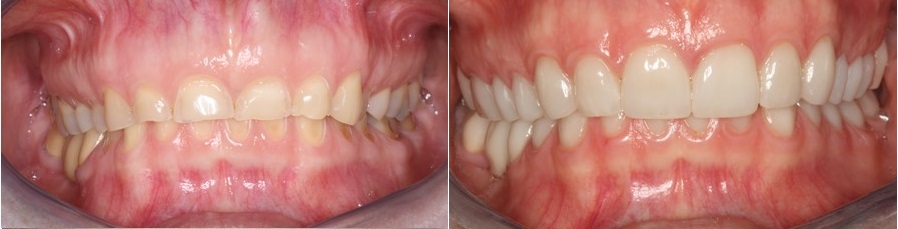

Στην φωτογραφία που ακολουθεί βλέπουμε την εικόνα των δοντιών της ασθενούς πριν και μετά την συγκόλληση των όψεων ρητίνης και πορσελάνης στα πρόσθια δόντια και των επένθετων πορσελάνης στα οπίσθια δόντια της άνω γνάθου.

Η εργασία γίνεται σταδιακά και όταν ολοκληρωθεί, όλα τα δόντια έχουν αποκατασταθεί στο νέο ύψος του προσώπου με ολοκεραμικές εργασίες οι οποίες αποδίδουν την μασητική μορφολογία, διορθώνουν όμως παράλληλα και μικρά αισθητικά προβλήματα στο χαμόγελο που είχε η ασθενής.

Το χαμόγελο της ασθενούς πριν και μετά την αποκατάσταση

Η εικόνα των δοντιών πριν και μετά την αποκατάσταση